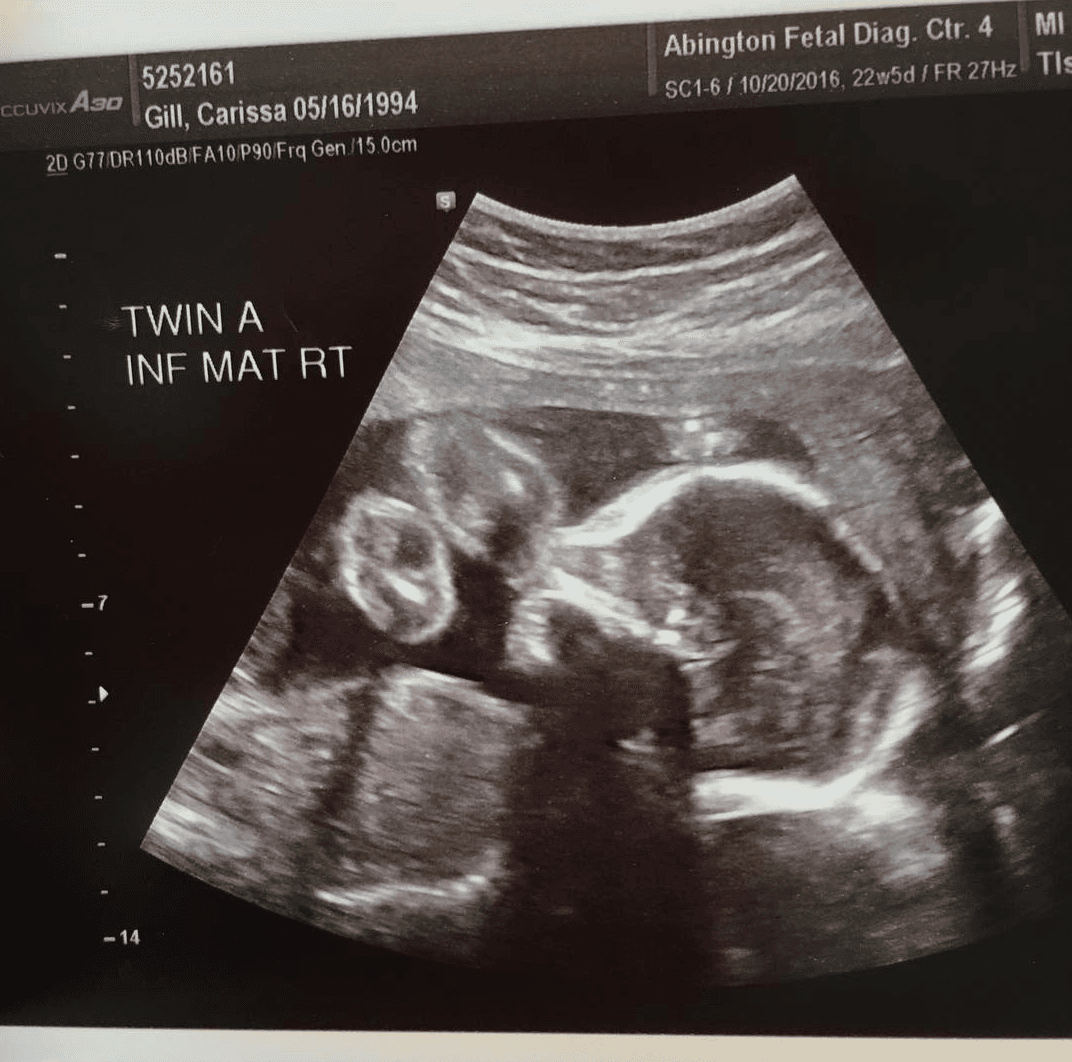

Abigail y Micaela Bachinskiy pasaron los primeros nueve meses de su vida unidas por la cabeza debido a una rara condición médica, conocida como craniopagus, que se presenta en uno de cada 2.5 millones de partos, de acuerdo con médicos de UC Davis. Los cráneos, tejidos y cerebros de las dos niñas estaban fusionados.

Los padres de las niñas, Liliya y Anatoliy Bachinskiy se enteraron de la condición en las primeras semanas del embarazo y acudieron a UC Davis Children's Hospital para hacer todos los arreglos del nacimiento. Los médicos comenzaron a estudiar cómo y cuándo sería la cirugía que las separaría y, tras meses de estudios y prácticas, lograron hacerlo el 23 y 24 de octubre.